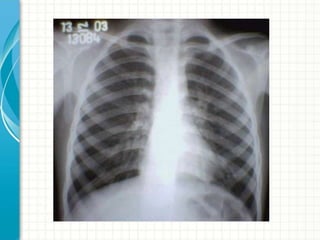

 Radiografia de tórax

Testes diagnósticos  Radiografiade tórax  Teste terapêutico  Espirometria com prova BD  Testes para atopia: cutâneos, IgE total e específica.